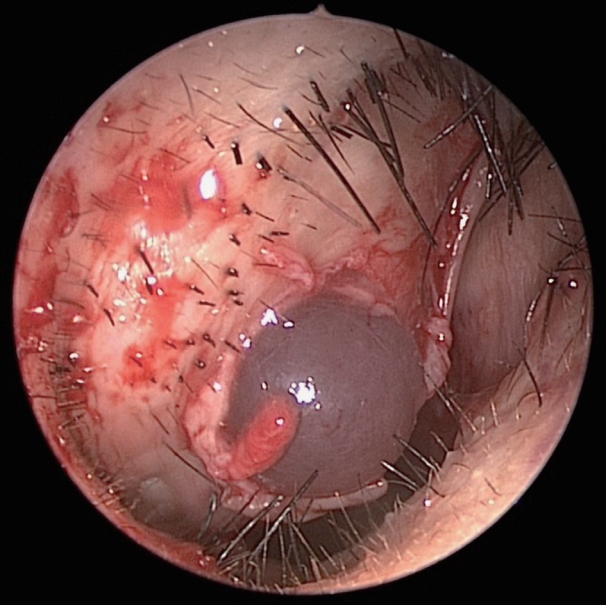

We performed endoscopic mass removal through the right nasal cavity. After an incision was placed in the right ala, the mass and the mucous membrane surrounding the mass were carefully peeled off and completely removed (Fig. 4). Histological examination confirmed the diagnosis of a myxoma (Fig. 5). After 9 months of surgery, patient is being followed up without complications or cosmetic problems (Fig. 6).

Radiographically, myxomas are usually well-defined ovoid masses with bony destruction or remodeling that show attenuation similar to that of water on CT [2]. On MRI, the tumor exhibits the signal intensity characteristic of fluid [6]. Intraoperatively, most masses are usually identified as glistering gelatinous masses which are oval or spherical in shape [2,4,7]. Histologic features of myxoma include spindled and stellate cells embedded in a fibromyxoid background [2,5,7,8]. Therefore, the definitive diagnosis of myxoma is made by microscopic examination to identify bland spindle cell myxoid lesion [2-6]. The spindled cells of myxoma will stain positively for vimentin and may show some positivity for S-100 protein and muscle-specific actin [2].